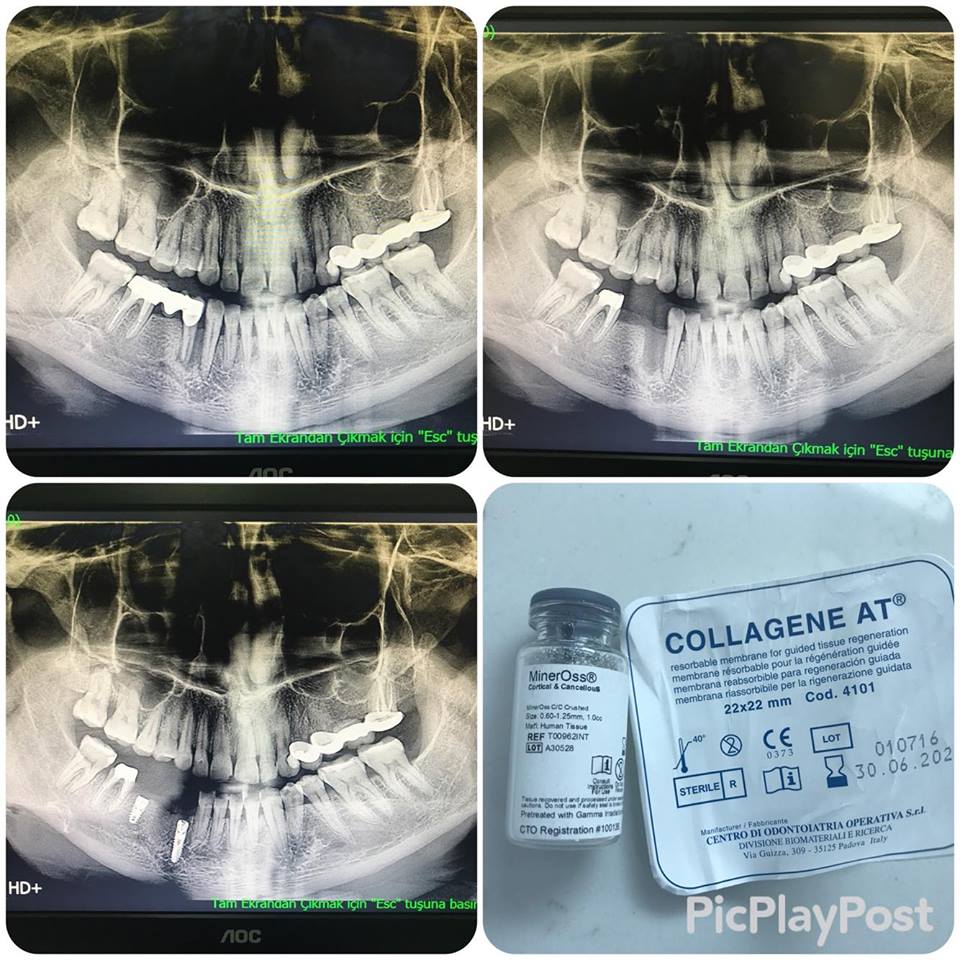

implant tedavisi